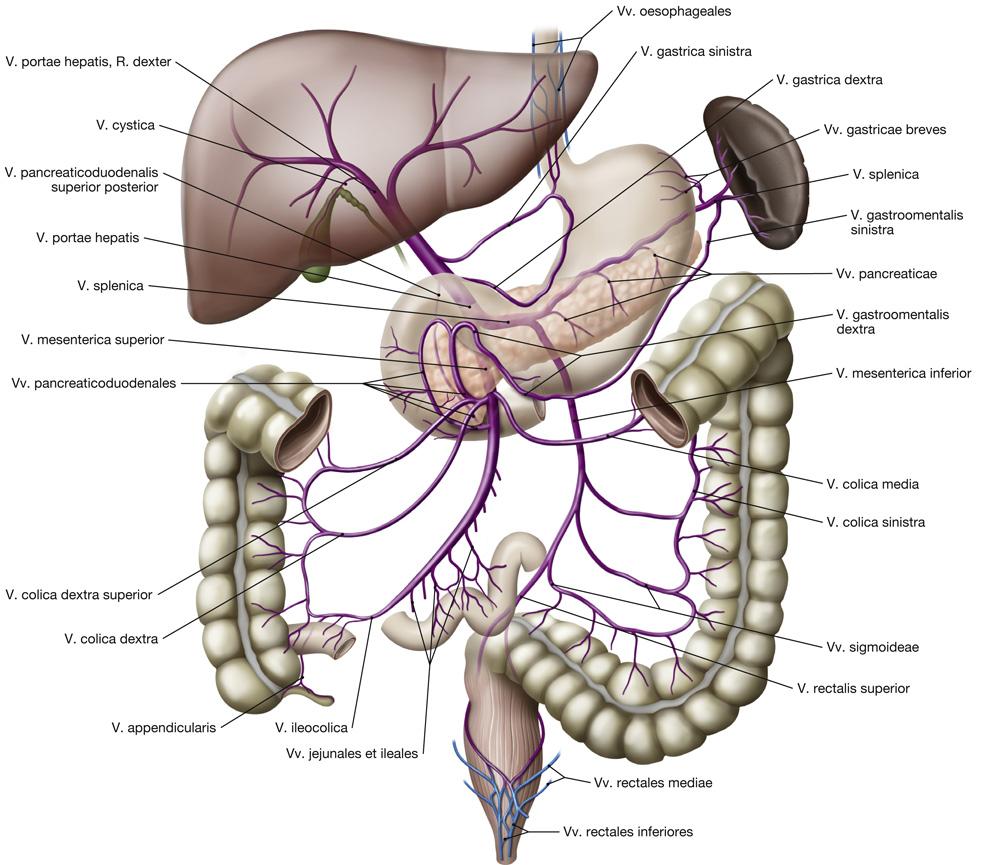

Fig 3.36: Vena portae hepatis

-

v portae

-

porto-cava shunt

bij blokkade v portae -

drie opties